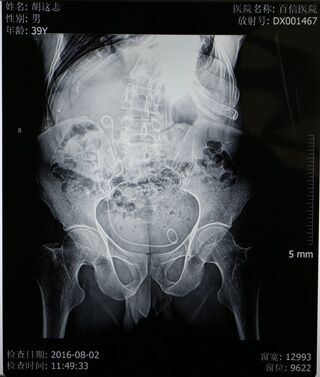

可这些也仅是体表上的显现,当丁主任拿到检查结果时是不免心头一紧——肌酐、尿素、尿酸等指标均超出正常指标数倍,已经开始呈现出尿毒症的检验结果及体征。患者的左肺已经从身体的右侧胸腔挤压到左侧胸腔,左侧肺功能已经有效消失,同时右侧肺功能也受到了影响,肺活量不到正常人的一半,呼吸很浅很快,并伴有呼吸性酸中毒,并且心脏功能很不好,平时还需要用药物来保持心率;但加严重的是患有结石的输尿管严重畸形,他的输尿管严重扭曲,左侧输尿管已蜿蜒扭转到身体右侧,从右侧延至膀胱。检查结果显示患者结石的位置还偏偏位于左侧输尿管上段,这也就意味着如果进行手术,则需要将输尿管镜一直蜿蜒延伸到输尿管的尽头才能进行,这些都使手术难度大幅度增加,在从医三十多年,临床经验非常丰富的丁主任看来,这个病例也是非常棘手的。